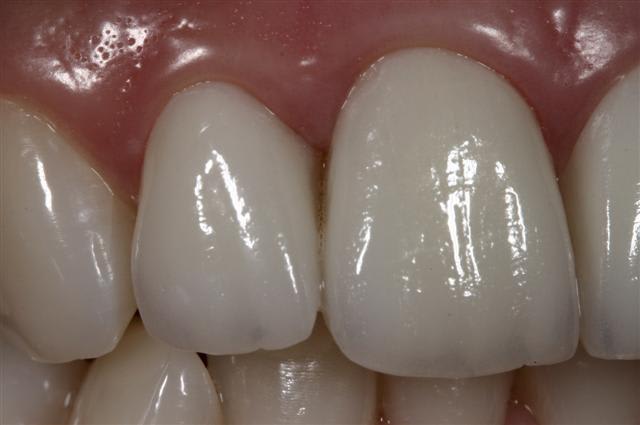

Quattres Empress 2...

et collées ...

J'ai mis Empress par habitude... ce sont des Emax.

oui taille définitive, vivante, collée au RelyX Transp